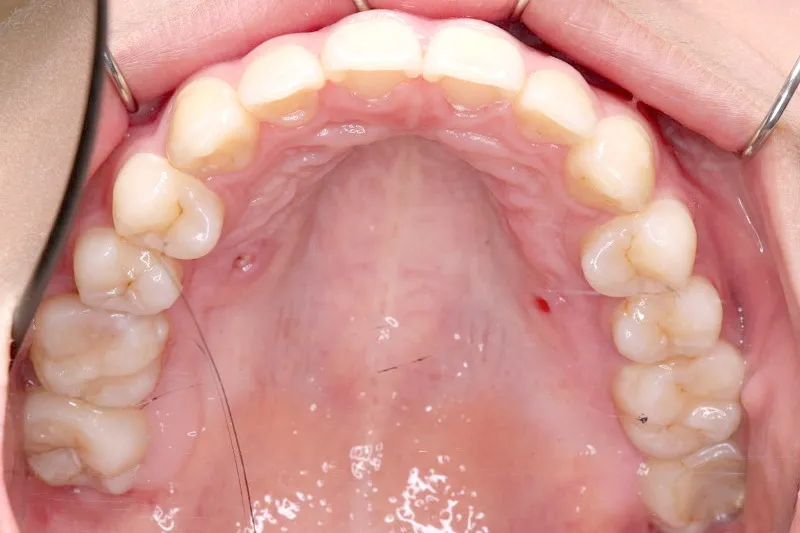

• 治療終了後

治療終了後

上下前から見える装置をつけ治療しました。歯は抜いてないです。

治療回数57回、6年9ヶ月の治療期間で矯正治療を終了しました。

主訴が改善され、ご満足頂きました。